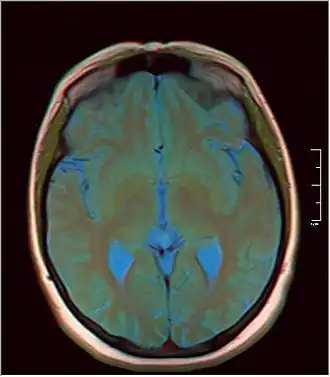

MRI axial in false color